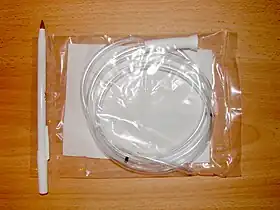

Stomach tube (Levin type), 18 Fr × 48 in (121 cm) | |